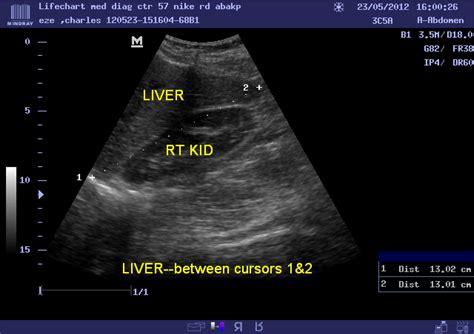

2. Ultrasound

This is the most common first-line test. It uses sound waves to create an image of the organ. It is highly effective at identifying structural abnormalities and measuring the dimensions of the liver lobes to see if they align with normal liver size standards.

Vertical Liver Span (Mid-clavicular) 10.5 cm to 15.5 cm

Transverse Diameter 20 cm to 23 cm

Anteroposterior Diameter 10 cm to 12.5 cm